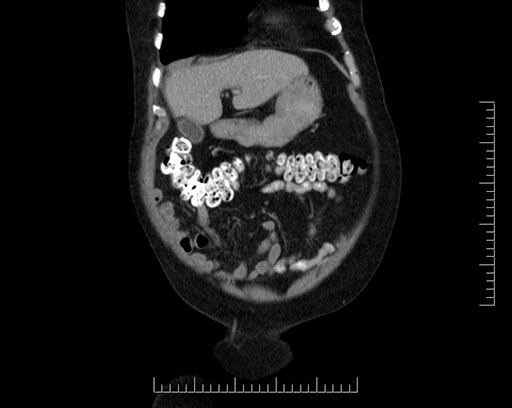

Imaging Analysis

Look through the patient's CT scan to identify any areas of concern for the necessary procedure.

Based on your CT findings, which issue(s) would give reason for "planned slowing down moment(s)" in this case?

Considering a standard Whipple procedure, what step(s) of the operation would you do differently in this case?